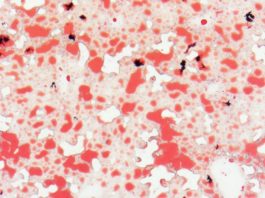

Лечение рака кожи при помощи умного геля

Различные разновидности меланомы – рака кожи – несмотря на свою очевидность и якобы легкий способ лечения традиционными...